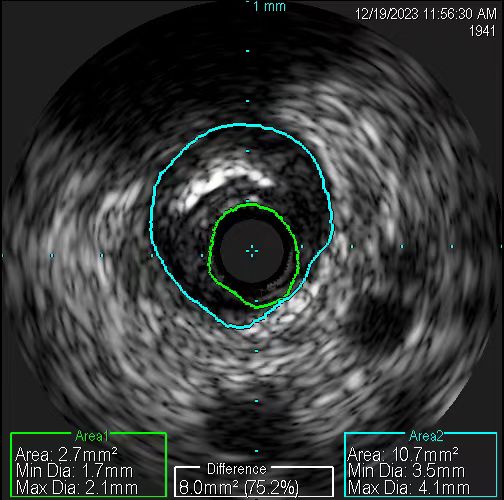

在无造影剂显影情况下,冠脉导丝能否送达病变血管远端,是手术的关键一步。操作稍有不慎,导丝就可能误入分支,也可能穿出血管,引发致命后果。患者及家属的充分信任,是手术得以进行的先决条件。12月19日11时许,在具备手术条件时,张慧晶带领手术小组成员开始了挑战。术前各项准备完成后,韩世飞在李占虎协助下将指引导管顺利放置于右冠开口,他依据丰富的手术经验,将导丝成功送入到右冠远端,血管内超声(IVUS)探头顺利到位后便开始进行精准的检查。结果提示:患者右冠原支架贴壁良好、膨胀充分,进一步证实了此次犯病不是源于右冠。再行前降支IVUS检查,依靠上次冠脉造影图像作为参照,指引导管、主支导丝顺利到位,反复多次进行IVUS检查。张宏博根据IVUS图像及时进行精准的测量,前降支近段最小管腔面积2.7mm2,中段斑块负荷重,均达到处理标准;远段血管直径约2.5mm,近段血管直径约3mm。张慧晶带领大家根据IVUS检查结果,制定了详尽的支架植入方案:应用血管内超声的换能器精准测量,辅以分支导丝做为路标,一举将支架成功释放到理想位置。最终经IVUS检查提示:支架膨胀充分、贴壁良好,无残余狭窄及边缘夹层。历时近2小时,手术过程顺利,全程未使用一滴造影剂,患者未出现任何不适及并发症。术后复查心脏超声较前无变化,无心包积液,确定了无穿孔发生。